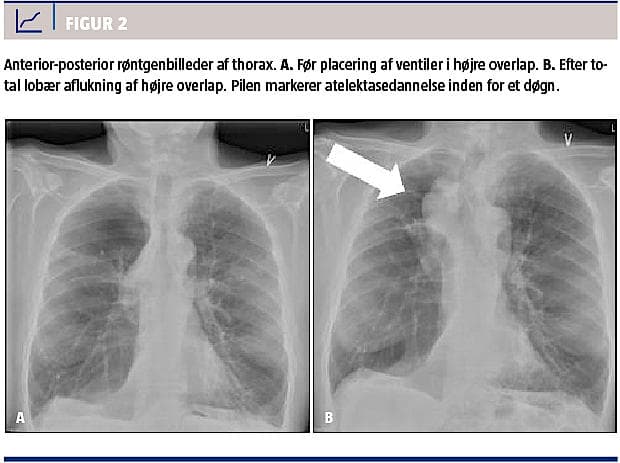

Princippet ved bronkoskopisk indsættelse af envejsventiler i luftvejene er aflukning af dele af lungen. Når ventilerne er placeret, kan der ikke længere komme luft ind i de behandlede segmenter, mens den eksisterende luft og eventuelt sekret kan passere ud af ventilen. På den måde dannes der en atelektase, og der opnås lungevolumenreduktion (Figur 2).